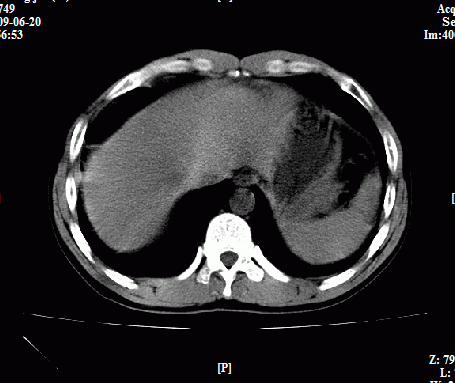

以下是引用随光逐影在2009-6-23 11:37:00的发言:[br]1)考虑胃癌;建议行胃镜检查进一步明确诊断。2)肝右叶肝内胆管结石(或钙化)。

以下是引用zxl51642在2009-6-23 11:31:00的发言:[br]胃大弯侧壁明显增厚呈软组织肿块,考虑胃癌可能性大,建议胃镜活检。